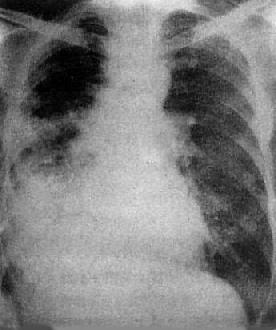

粟粒型肺结核病灶小,透视常难以辩认,故拟诊急性粟型肺结核时应摄片检查。病变早期整个肺野可呈毛玻璃样密度增高。约10日后可出现均匀分布的1.5~2mm大小、密度相同的粟粒状病灶,正常肺纹理常不能显示(图3-1-22)。经过适当治疗后。病灶可在数月内逐渐吸收,偶尔以纤维硬结或钙化而愈合。病变恶化时,可以发生病灶融合,表现为病灶增大,边缘模糊,甚至形成小片状或大片状影,并可干酪样化而形成空洞。

图3-1-22 急性粟粒型肺结核

两肺野布满粟粒状病灶,分布均匀,肺门大

(2)亚急性或慢性血行播散型肺结核:系少量结核杆菌在较长时间内多次进入血流播散至肺部所致。患者抵抗力较强,症灶多以增殖为主,临床症状可不明显或有反复的发热、畏寒或轻度结核中毒症状如低热、盗汗、无力、消瘦等。

由于病灶系多次血行播散所形成,故X线表现为大小不一、密度不同、分布不均的多种性质的症灶(图3-1-23)。小者如粟粒,大者可为较大的结节状,主要分布于两肺上、中野,下野较少。早期播散的症灶可能已经钙化,而近期播散的病灶仍为增殖性或渗出性。本型结核发展较慢,经治疗新鲜病灶可以吸收,陈旧病灶多以纤维钙化而愈合。恶化时病灶可融合并形成空洞或逐渐转为慢性纤维空洞型肺结核。

图3-1-23 慢性血行播散型肺结核

两肺野布满大小不一、密度不同、分布不均的病灶,

下野较少,膈位置低而平